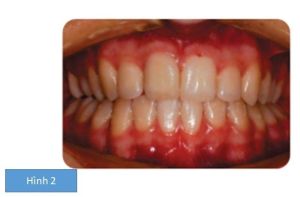

Bệnh nhân nữ 13 tuổi có sai khớp cắn hạng II tiểu loại 2 trên nền xương hạng II nhẹ với giảm kích thước dọc. Có sự chen chúc nặng ở cả 2 hàm răng, các răng hàm lớn vĩnh viễn thứ nhất bên trái đã có phục hồi lớn và sâu răng ở R47 (Hình 1)

- Nhổ R15 ngầm, R26, R44 và R36

- Chen chúc nặng ở hàm dưới với R35 và R44 mọc kẹt do thiếu khoảng

- Ở cung hàm trên, nhóm răng phía sau bị chen chúc nặng với cả 2 răng hàm nhỏ thứ 2 hàm trên mọc ngầm về phía vòm miệng. Nhóm răng trước hàm trên chen chúc mức độ vừa, cả 2 răng nanh nằm lệch má.

Độ nghiêng gần –xa của răng nanh: Tất cả các răng nanh đều nghiêng xa. Điều này đặc biệt đáng kể ở cung răng trên, nên làm tăng neo chặn trong giai đoạn nắn thẳng hàng nhóm răng trước hàm trên.

Độ nghiêng ngoài – trong của nhóm răng trước hàm trên: nhóm răng trước hàm trên đều ngả sau, điều này yêu cầu đặt torque để cải thiện độ nghiêng ngoài – trong của răng.

- Cần sửa đường giữa ở cả 2 cung răng.

- R44 được nhổ vì chen chúc nặng và lệch lạc.

- Quyết định nhổ cả 2 răng: R26 và R36 dựa trên tình trạng của 2 răng này do cả 2 răng đều đã được trám phục hồi. Việc loại bỏ những răng này sẽ cung cấp đủ khoảng trống để giải phóng chen chúc ở nhóm răng sau.

- Ở cung răng trên, R15 chưa mọc và lạc chỗ bị nhổ do vị trí của nó không thuận lợi.